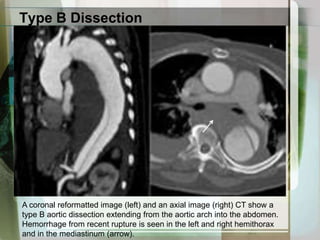

Type B DissectionA coronal reformatted image (left) and an axial image (right) CT show a type B aortic dissection extending from the aortic arch into the abdomen. Hemorrhage from recent rupture is seen in the left and right hemithoraxand in the mediastinum (arrow).

Type B DissectionAcoronal reformatted image (left) and an axial image (right) CT show a type B aortic dissection extending from the aortic arch into the abdomen. Hemorrhage from recent rupture is seen in the left and right hemithoraxand in the mediastinum (arrow).